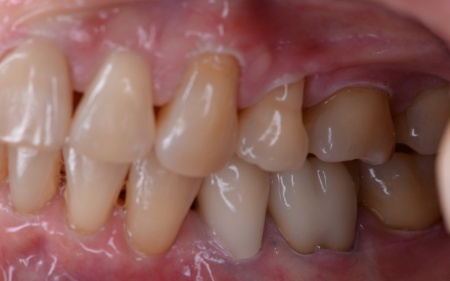

患者様は、歯並びと噛み合わせの根本的な改善を希望されています。

そのため、ワイヤー矯正である程度歯の移動を行ったのち、アライナー矯正(マウスピース矯正)で仕上げを行う矯正治療を提案し、同意いただきました。

まずはワイヤー矯正を行い、ある程度まで歯並びを整えます。

その後アライナー矯正に移行し、正しい歯並びになるよう調整を行いました。

最後に、噛み合わせや前歯の隙間が改善されたことを確認して、治療を終了しています。